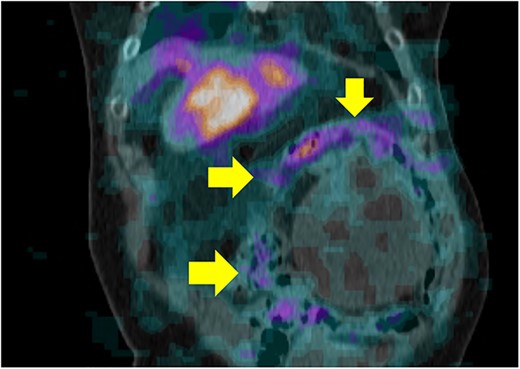

An 87-year-old female, with no past medical history, was admitted to the emergency center in our tertiary institution with a 1-month history of abdominal pain and discomfort. Initial workup using abdomino-pelvic computed tomography (APCT) presented a 16-cm-sized heterogeneous tumor in the left adrenal gland (Fig. 1). She was referred to the endocrine department for further evaluation. The results of laboratory tests, including those for measuring plasma levels of adrenocorticotrophic hormone, cortisol, aldosterone, epinephrine, norepinephrine, metanephrine, dehydroepiandrosterone sulfate as well as urine levels of epinephrine, norepinephrine, metanephrine, vanillylmandelic acid and homovanillic acid were within normal limits. Plasma renin activity was also normal. The levels of serum markers for carcinoma were within normal limits radiolabeled metaiodobenzylguanidine single photon emission computed tomography (I-123 MIBG SPECT) presented a huge mass with mild peripheral uptake of the left adrenal gland (Fig. 2). Finally, positron emission tomography (PET) was done for evaluation of distant metastasis. PET showed the accumulation of fluorodeoxyglucose (FDG) in the left adrenal tumor with [maximum standardized uptake value (SUVmax: 7.4)] and lymph nodes in the para-aortic area (SUVmax: 2.4; Fig. 3). We initially expected adrenocortical carcinoma with lymph nodes metastasis.

PET showed the accumulation of FDG in the left adrenal tumor and lymph nodes in the para-aortic area.